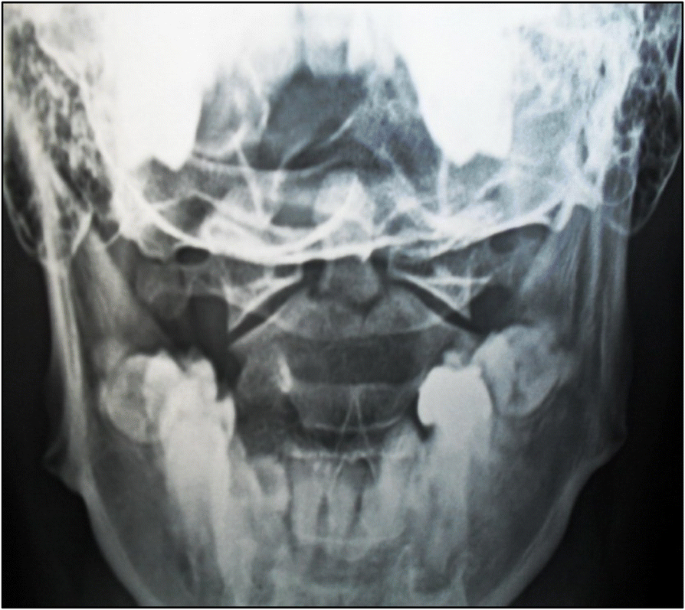

odontoid fx

fx of dens and/or lateral masses or arches of C2, demoed by open mouth view